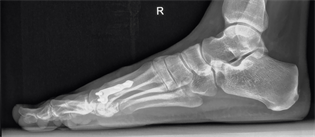

Figure 27. Patient Nr. 5: Hallux valgus with pronation, elevation, malrotation and pathological DMAA.

Figure 28. Patient Nr. 5: Correction of all components, only partial contact of bone partners, additional FDL Transfer II for a flexible hammertoe II.

Figure 29. Patient Nr. 5. Result after 8 years.